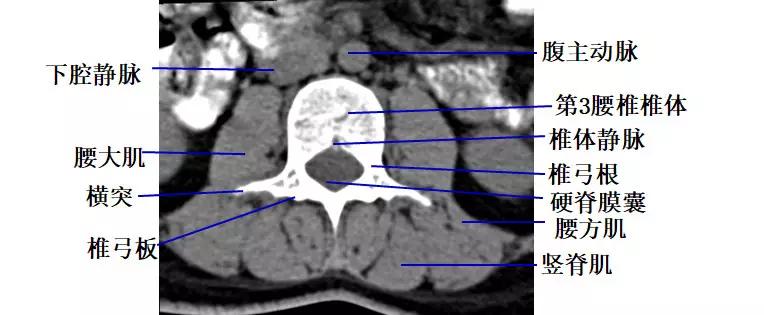

腰段横断面解剖及影像

1.经腰椎椎弓根的横断层面(CT)

2.经腰椎椎体下部的横断层面(CT)

二、腰 椎

L1-2至L4-5的椎间盘形态大致相似,呈肾形,后缘年轻人稍凹,凹陷部与后纵韧带走行一致,随着年龄的增长,后缘可变得平直。

正常L5-S1椎间盘的后缘较平直,并可轻微膨出。

椎间盘由髓核和纤维环组成,略高于软组织密度影,CT值为80~120HU,CT不能区分髓核和纤维环。

黄韧带厚约2~4mm,超过5mm为肥厚。

正常小关节面光滑、完整,关节间隙为2~4mm。

椎基静脉影

椎间孔前为椎体,后为椎小关节,上下为椎弓根,内与侧隐窝相连,有脊神经根通过。

侧隐窝:向下外续于椎间孔,有脊神经经过:前壁为椎体后外缘;后壁为上关节突前面与黄韧带;外界为椎弓根。

正常前后径为3-5mm,<3mm侧隐窝狭窄>5mm,肯定不狭窄。